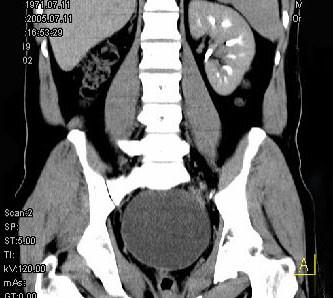

问题 男,34岁,右下腹持续性隐痛半月,排尿时加重入院,CT检查如图所示,下列说法错误的是 ( )

选项 A、该囊性病变考虑来源于精囊 B、此囊性病变为右精囊腺囊肿 C、膀胱右后下方囊性病变 D、膀胱向下,向后移位 E、右肾缺如

答案 D